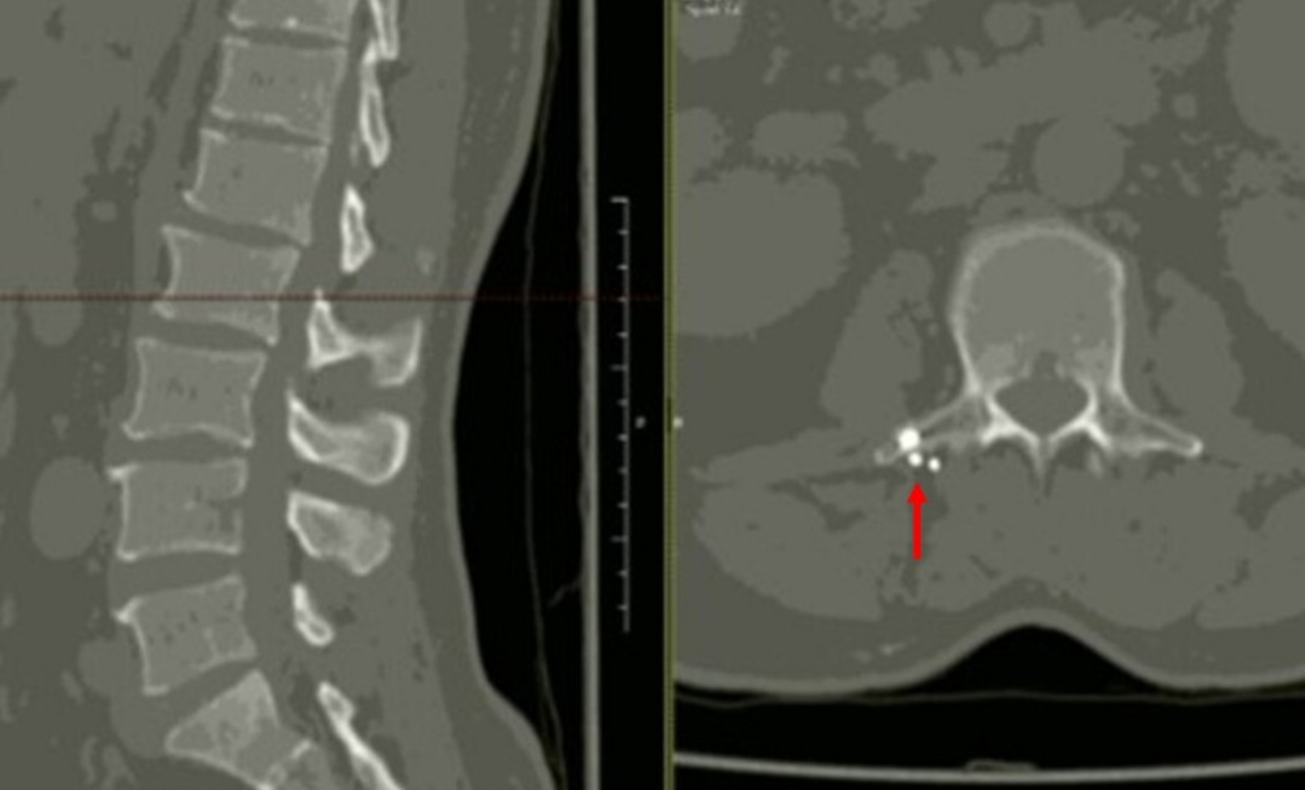

İki yıl önce sivil bir ateşli silah yaralanması sonrası L2 vertebrasında şarapnel parçaları bulunan 28 yaşındaki erkek hasta kronik bel ağrısı ile başvurdu. Hastaya daha önce NSAİİ’ler, gabapentinoidler, antidepresanlar ve opioidler dâhil olmak üzere çeşitli farmakolojik tedaviler uygulanmasına rağmen yeterli ağrı kontrolü sağlanamamıştı. Omurgada yabancı cisim bulunması nedeniyle epidural girişimlerden kaçınıldı. Alternatif bir yöntem olarak T12 seviyesinde ultrason eşliğinde erektör spina plan bloğu (ESPB) uygulandı. İşlem sonrası hastada hızlı ve belirgin ağrı azalması sağlandı; ağrı skorlarında, mobilitede ve yaşam kalitesinde kalıcı iyileşme gözlendi. Bir yıllık takip süresince komplikasyon ya da semptom nüksü izlenmedi ve hasta ek analjezik girişimlere ihtiyaç duymadı. Bu olgu, omurgada retansiyonlu yabancı cisim bulunan ve geleneksel girişimsel yöntemlerin kontrendike olduğu hastalarda ESPB’nin kronik post-travmatik bel ağrısı tedavisinde güvenli ve etkili bir seçenek olabileceğini göstermektedir.